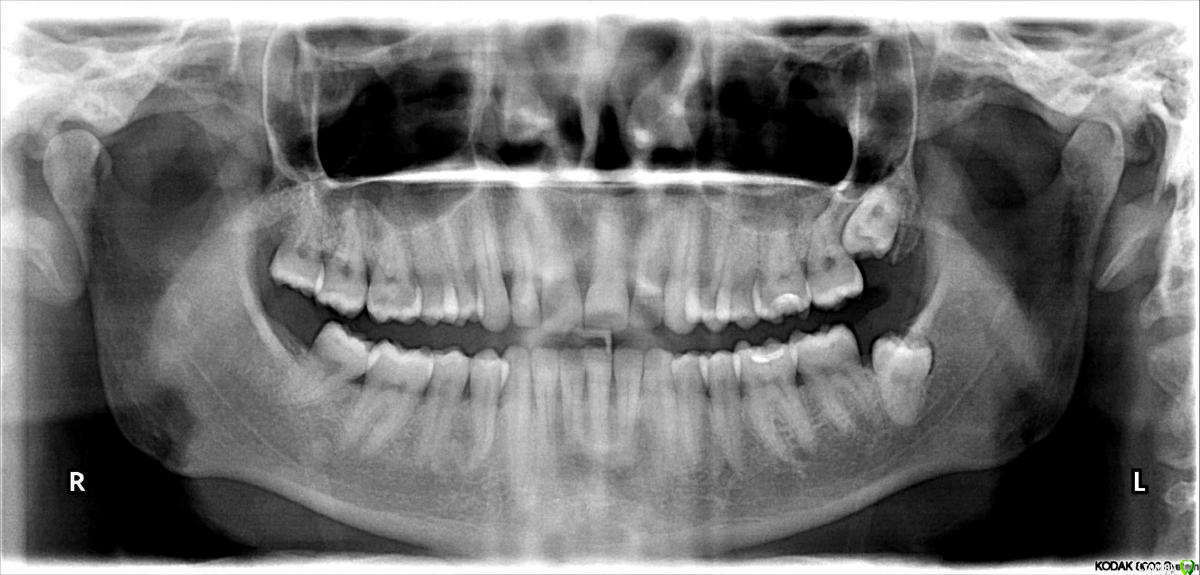

fap Опубликовано 19 января, 2015 Автор Поделиться Опубликовано 19 января, 2015 (изменено) ПожалуйстаP.S. Снимок от июня 2014 до лечения. В том числе до пломбирования. Изменено 19 января, 2015 пользователем fap Ссылка на комментарий

fap Опубликовано 20 января, 2015 Автор Поделиться Опубликовано 20 января, 2015 (изменено) Спасибо.Пародонтит подтверждается по ОПГ? Какой степени/стадии?От карманов принципиально можно избавиться или хотя бы значительно уменьшить глубину? (есть и 5-6-7 мм, особенно на молярах) Что делать с рецессией? На 2-3 зубах она заметна, на остальных нет. Какие еще проблемы видны на снимке? В частности, что делать с 8-ками?Из 4-ых есть только одна, остальные так и не вылезли. На приёме доктора говорили не трогать, если не беспокоят. А они не беспокоят. Изменено 20 января, 2015 пользователем fap Ссылка на комментарий

red_butler Опубликовано 20 января, 2015 Поделиться Опубликовано 20 января, 2015 Пародонтит подтверждается по ОПГ? Какой степени/стадии? ОПГ дополнительный метод обследования, для постановки диагноза нужен осмотр и зондирование пародонтальных карманов Что делать с рецессией? На 2-3 зубах она заметна, на остальных нет. выкладывайте фото Какие еще проблемы видны на снимке? В частности, что делать с 8-ками? Из 4-ых есть только одна, остальные так и не вылезли. зубы мудрости удаляйте Ссылка на комментарий